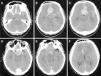

The present report describes the case of a patient with a history of pituitary macroadenoma, who had undergone a partial transsphenoidal resection ten years earlier. Admission to our service occurred after a sudden headache followed by mental confusion. A cranial computed tomography showed subarachnoid haemorrhage and expansive suprasellar lesion. Cerebral angiography showed a saccular aneurysm of the anterior communicating complex. The patient underwent a surgical procedure for microsurgical clipping of the aneurysm and partial resection of the pituitary tumour. We have also included a brief review of the literature on this subject.

El presente informe describe el caso de una paciente con antecedentes de macroadenoma hipofisario, que fue sometido a una resección transesfenoidal parcial diez años antes. La entrada a nuestro servicio se produjo después de que un dolor de cabeza repentino seguido por la confusión mental. Una tomografía computarizada craneal mostró hemorragia subaracnoidea y lesión supraselar expansiva. La angiografía cerebral mostró un aneurisma sacular del complejo comunicante anterior. El paciente se sometió a un procedimiento quirúrgico para clipaje de aneurisma y la resección parcial del tumor pituitario. También hemos incluido una breve revisión de la literatura sobre este tema.